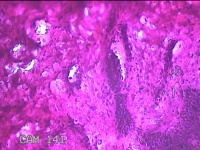

臀部肿物

性别

女

年龄

32岁

临床诊断

脂溢性角化病;皮肤感染

一般病史

颈部臀部丘疹数年。

标本名称

大体所见

灰白粉红色带皮肤样肿物1.8x0.5x0.2cm一个,表面糜烂。

图3